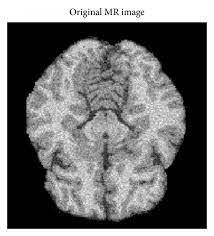

Acquirementisthefirstandforemoststep intumordetectionprocess.Itistheactionof retrievinganimagefromaMRIMachine.The detectionprocesscannotdoanyactualandformal processingwithoutanMRIimage.MRIisan especiallytechnologicalelaborationinthemedical fieldthatyieldsimageswithextraordinarytenacity tosenseandthencancategorizeillnessesthatare inventintheorgansofthesickperson’sbody.One situationispossibletoidentifyfromreadinganMRI imagewithin2.56×1011Nanoseconds.The followingviewexplainsthebrainanditsangles. ThefollowingfigureshowsthesamplebrainMRI fromRealPatientDatabase.

Fig 2: a) SingleBrain MRI b) Brain View with different angle